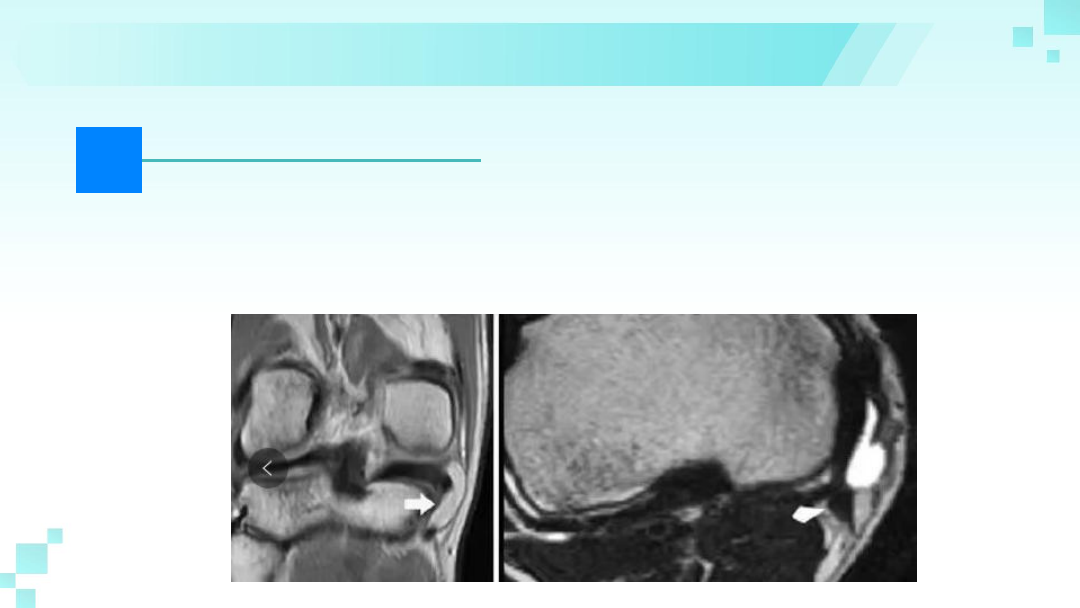

磁共振成像(MR)可以清晰显示鹅足区

解剖结构及病变。

鹅足肌腱炎磁共振表现为膝关节后内侧、

内侧副韧带之间的鹅足滑囊区T1WI低信

号、脂肪抑制加权像(FS PDWI)呈高信

号影像。